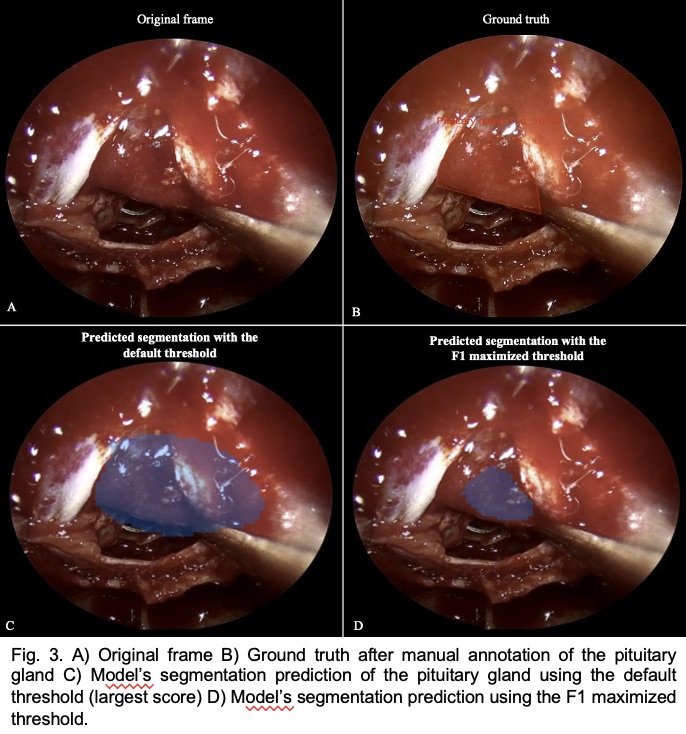

Sport-related concussion poses significant diagnostic challenges due to its subtle, transient nature and lack of identifiable biomarkers. To capture the changes from injury holistically, we integrated advanced neuroimaging with quantitative robotic assessment: Diffusion Tensor Imaging (DTI) and Neurite Orientation Dispersion and Density Imaging (NODDI) were used to detect acute microstructural white matter changes, while the Kinarm robotic platform objectively measured sensorimotor function via the Reverse Visually Guided Reaching (RVGR) task. This multimodal approach was applied to 12 concussed athletes (21 ± 2.1 y; 9 M/3 F; tested ~7 days post-injury) and 24 matched controls (21 ± 2.5 y; 11 M/16 F) to bridge structural and functional insights.

Significanttractswithsphere Noun slideshow grey Rvgrmethods

Behaviour (RVGR): Failed to detect functional deficits in the same acute period.

Screenshot 2025 05 30 at 11.49.38 pm

Neuroimaging (DTI/NODDI): Highly sensitive, revealing significant acute microstructural alterations in key white matter tracts.

Best correlation matrixnew page 0001

Conclusion

Our findings demonstrate that acute sport-related concussion induces detectable microstructural alterations in specific white matter tracts (↑FA, ↓MD/RD/Viso), yet these changes occur without concurrent deficits in sensorimotor performance on the precise Kinarm RVGR task. This critical disconnect underscores that advanced diffusion MRI (DTI/NODDI) is highly sensitive for detecting subclinical brain injury, revealing underlying pathology that standard functional assessments may miss. Consequently, relying solely on behavioural measures risks underestimating injury severity and compromising athlete safety. Multimodal assessment protocols, integrating both advanced neuroimaging and quantitative functional tools, are therefore essential for accurate diagnosis, informed return-to-play decisions, risk stratification, and targeted rehabilitation strategies following concussion.